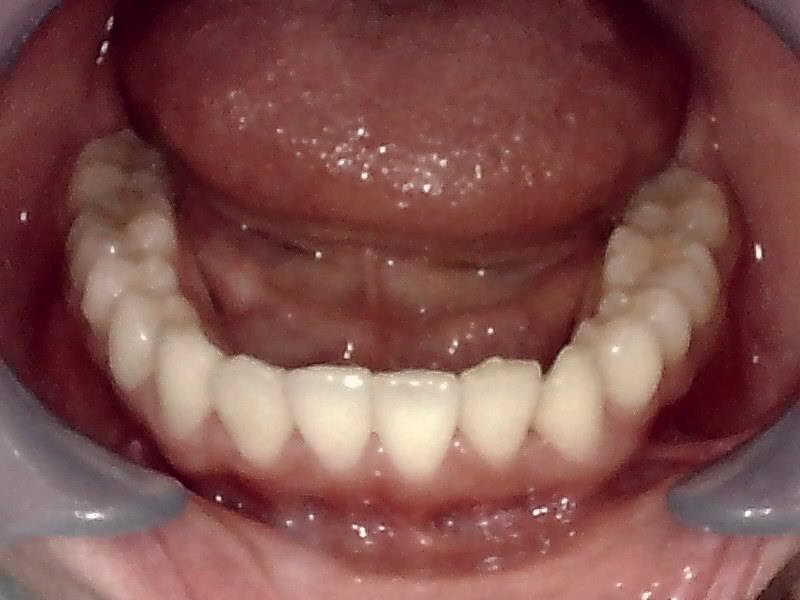

下顎